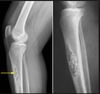

What is this lesion?

Chondrosarcoma The gross image shows a destructive cartilaginous lesion

Dedifferentiated chondrosarcoma ## Footnote The histology pic shows a cartilaginous tumor juxtaposed to a high grade sarcoma This gross lesion is showing blue/grey cartilage tumor juxtaposed to a fleshy, tan/white sarcomatous tumor. Variable amounts of 2 components so careful sampling!